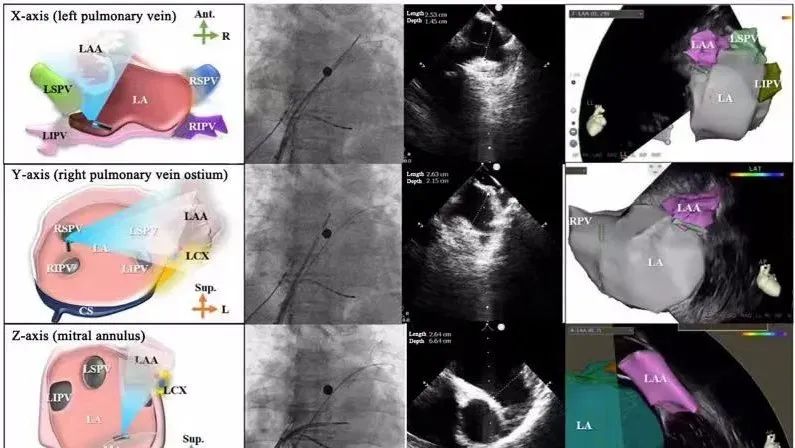

一種與心導(dǎo)管檢查相結(jié)合的超聲心動(dòng)圖診斷新興技術(shù),通過將超聲探頭置于心腔內(nèi)部,發(fā)射并接收超聲信號(hào),來精確獲取心臟解剖結(jié)構(gòu)、心臟血流動(dòng)力學(xué)等信息的實(shí)時(shí)成像。與其他影像技術(shù)相比,ICE技術(shù)具有操作簡單、無輻射、安全性高、手術(shù)效率高、實(shí)用等優(yōu)勢,ICE在很大程度上有望取代經(jīng)食道超聲心動(dòng)圖(TEE),成為電生理和結(jié)構(gòu)性心臟病領(lǐng)域的理想成像方式。

目前ICE技術(shù)已被應(yīng)用于左心耳封堵、房顫射頻消融、二尖瓣成形、房間隔缺損封堵等多種心臟介入手術(shù),應(yīng)用場景主要圍繞心臟電生理、結(jié)構(gòu)性心臟病等領(lǐng)域,目前以電生理應(yīng)用為主。數(shù)據(jù)顯示,我國結(jié)構(gòu)性心臟病介入器械市場規(guī)模已從2017年的4億元增長至2021年的20億元,年復(fù)合增長率達(dá)48.3%;預(yù)計(jì)到2025年,該市場規(guī)模將達(dá)到104億元,可以預(yù)見ICE市場規(guī)模也將同步高速增長,未來市場發(fā)展空間廣闊。

心腔內(nèi)超聲(ICE)技術(shù)壁壘極高,國內(nèi)主要廠商核心部件仍舊為進(jìn)口,集成了超聲和圖像處理最前端技術(shù),包括超聲探頭、線纜、軟件成像算法等,是當(dāng)前內(nèi)窺超聲方向最具挑戰(zhàn)的領(lǐng)域。ICE的應(yīng)用經(jīng)歷了2D平面成像、3D三維立體成像、以及4D的實(shí)時(shí)三維立體成像階段。